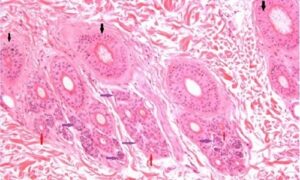

Transverse sectioning in the evaluation of skin biopsy specimens from alopecic dogs by Professor Ross Bond and colleagues at the RVC

This study showed that transverse sectioning confers significant benefits and complements traditional vertical sectioning in the histological assessment of canine hair follicle diseases.

Skin biopsy specimens were taken from skin lesions in 31 alopecic dogs clinically suspected of having a range of atrophic, dysplastic and inflammatory diseases of hair follicles and/or adnexal glands. Fixed samples were bisected vertically and one half was embedded in the traditional vertical orientation, whilst the other half was sectioned transversely. Sections were reviewed independently and the kappa statistic was used to assess the agreement between histological findings from both section types.

Read more and access the publication